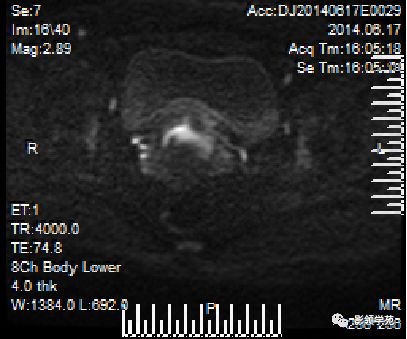

DWI:局限性高信号,癌组织ADC值<癌旁组织<小于正常宫颈组织

宫颈癌术后复发患者,DWI上病灶较T2 fs及T1+C更加明显